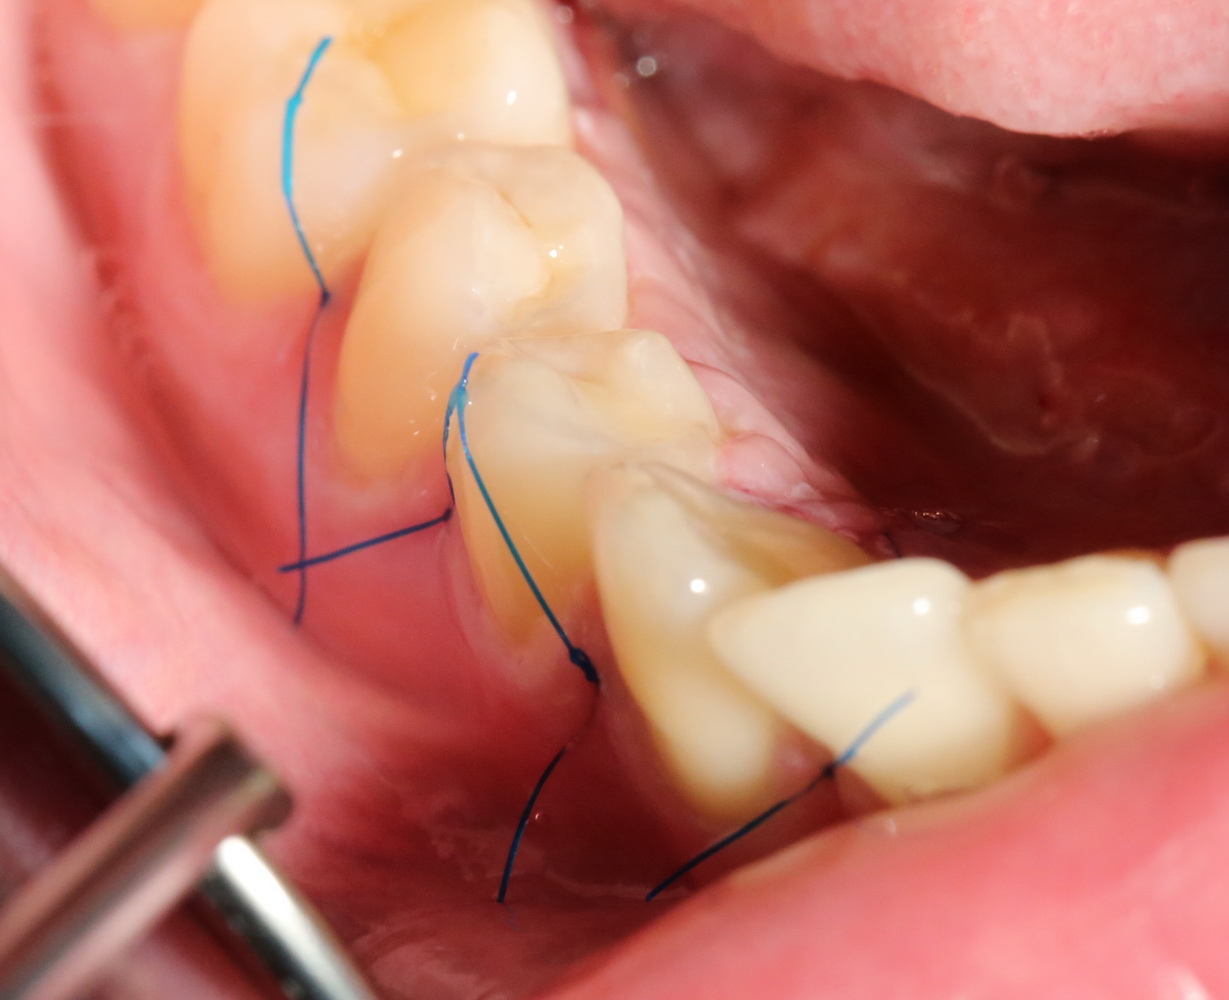

Всё начинается с анестезии и разреза:

Его приблизительная схема показана на картинке справа. Разрез спланирован таким образом, чтобы потом вывести узелки швов на внешнюю сторону — так они будут меньше беспокоить пациента в послеоперационном периоде. К тому же, обзор раны будет лучше.

Для разреза я пользуюсь специальным обоюдоострым микроскальпелем, кстати.

Следует учесть, что с язычной стороны слизистая оболочка более нежная и тонкая. Скелетировать альвеолярный отросток нужно с большой осторожностью:

Белой стрелочкой я отметил сосудистые пучки, входящие-выходящие в/из альвеолярного отростка. Некоторые ошибочно принимают их за нервы и этим объясняют то, что анестезия не подействовала. Напомню, что местная анестезия не действует только тогда, когда ее делают неправильно.

Черный пунктир — это примерная схема костнопластической трепанации. За последние годы я серьезно «подсел» на ультразвук — делаю им любые серьезные операции.